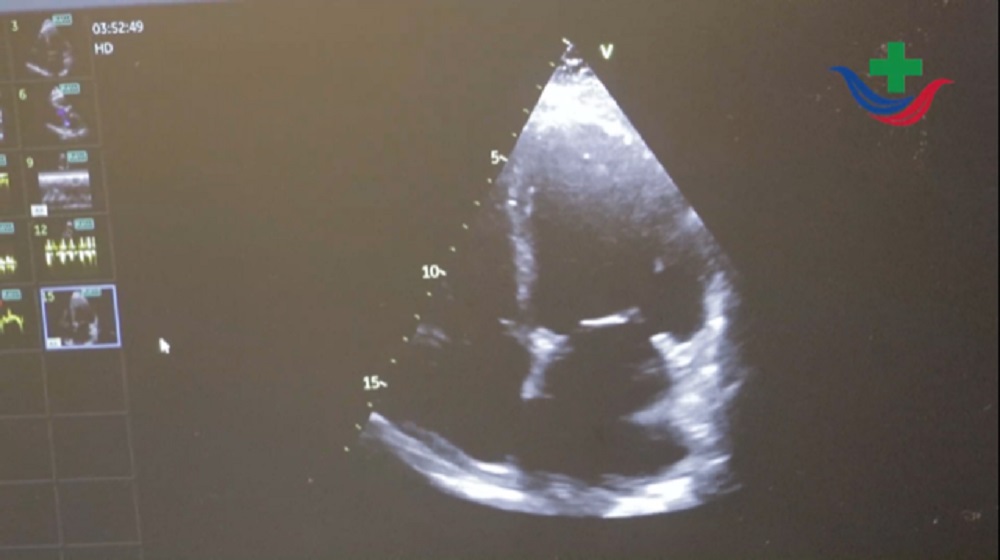

“En el Hospital Escuela se realizan eco doppler cardíacos, de vasos de cuello, ecotransesofágicos, ecoburbujas, ecoestrés, todo lo que tiene que ver con la ecografía cardíaca, arterial y venosa”; a lo que agregó en cuanto a la relación del personal con que cuentan que “son 10 ecocardiografistas en el sector, que se especializan en algún tipo de ecografía”.

En relación a la especialidad, la profesional explicó que es una prestación multidisciplinaria “se atienden a pacientes que están internados en clínica médica, en cirugía, en terapia, unidad coronaria, son pacientes que requieren algún tipo de estudio cardiológico o vascular cuando tienen catéter venosos, abarcamos todos los servicios que requieran estudios”.